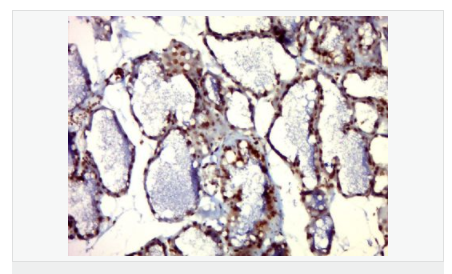

產品應用WB=1:500-2000 ELISA=1:5000-10000 IHC-P=1:100-500 IHC-F=1:100-500 IF=1:100-500 (石蠟切片需做抗原修復)

細胞定位細胞核 細胞漿 細胞膜

免 疫 原KLH conjugated Synthesised phosphopeptide derived from human PIM1 around the phosphorylation site of Tyr309:HR(p-Y)HG

產品介紹The protein encoded by this gene belongs to the Ser/Thr protein kinase family, and PIM subfamily. This gene is expressed primarily in B-lymphoid and myeloid cell lines, and is overexpressed in hematopoietic malignancies and in prostate cancer. It plays a role in signal transduction in blood cells, contributing to both cell proliferation and survival, and thus provides a selective advantage in tumorigenesis. Both the human and orthologous mouse genes have been reported to encode two isoforms (with preferential cellular localization) resulting from the use of alternative in-frame translation initiation codons, the upstream non-AUG (CUG) and downstream AUG codons (PMIDs:16186805, 1825810).[provided by RefSeq, Aug 2011].

Proto-oncogene with serine/threonine kinase activity involved in cell survival and cell proliferation and thus providing a selective advantage in tumorigenesis. Exerts its oncogenic activity through: the regulation of MYC transcriptional activity, the regulation of cell cycle progression and by phosphorylation and inhibition of proapoptotic proteins (BAD, MAP3K5, FOXO3). Phosphorylation of MYC leads to an increase of MYC protein stability and thereby an increase of transcriptional activity. The stabilization of MYC exerced by PIM1 might explain partly the strong synergism between these two oncogenes in tumorigenesis. Mediates survival signaling through phosphorylation of BAD, which induces release of the anti-apoptotic protein Bcl-X(L)/BCL2L1. Phosphorylation of MAP3K5, an other proapoptotic protein, by PIM1, significantly decreases MAP3K5 kinase activity and inhibits MAP3K5-mediated phosphorylation of JNK and JNK/p38MAPK subsequently reducing caspase-3 activation and cell apoptosis. Stimulates cell cycle progression at the G1-S and G2-M transitions by phosphorylation of CDC25A and CDC25C. Phosphorylation of CDKN1A, a regulator of cell cycle progression at G1, results in the relocation of CDKN1A to the cytoplasm and enhanced CDKN1A protein stability. Promote cell cycle progression and tumorigenesis by down-regulating expression of a regulator of cell cycle progression, CDKN1B, at both transcriptional and post-translational levels. Phosphorylation of CDKN1B,induces 14-3-3-proteins binding, nuclear export and proteasome-dependent degradation. May affect the structure or silencing of chromatin by phosphorylating HP1 gamma/CBX3. Acts also as a regulator of homing and migration of bone marrow cells involving functional interaction with the CXCL12-CXCR4 signaling axis.

PIM1蛋白是絲氨酸/蘇氨酸蛋白激酶2家族成員,他參與細胞信號轉導、細胞凋亡、轉錄調節(jié),在很多腫瘤中表達,尤其是前列腺癌,表達水平較高。